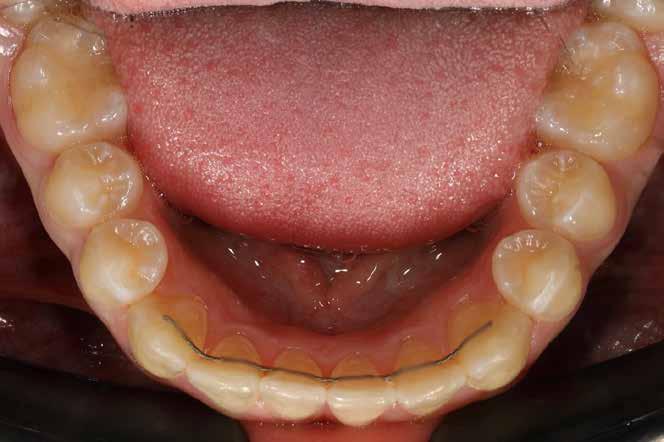

Minden fogszabályozó kezelés után nagyon fontos a retenció, de ilyen eltérés esetén különösen, mivel a recidíva veszély nyitott harapás esetén a legnagyobb. A fogak és a harapás megtartása fix és kivehető retainer-ekkel történik.

A kivehető helyben-tartók legfontosabb eleme a mindkét fogívet összekötő ún. Splint (19. kép), amely egyrészt saggitálisan tartja a helyén a mandibulát, hogy ne csússzon vissza hátrafelé, másrészt segít a harapás zártan tartásában a növekedés teljes befejeződéséig.